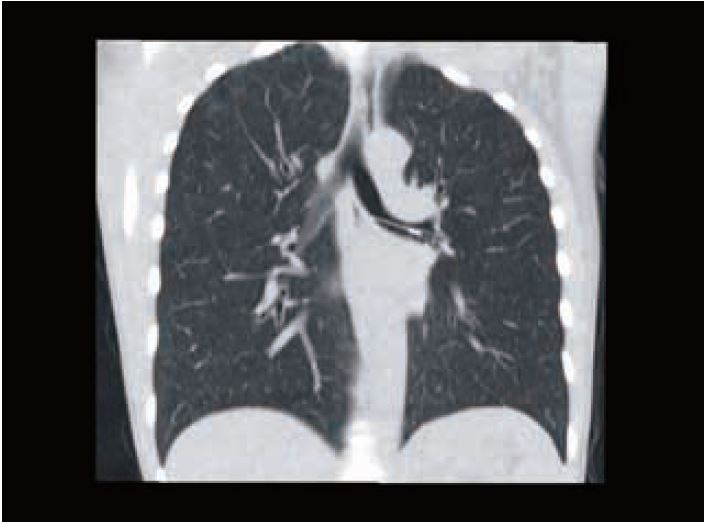

Наші типові пацієнти для обстеження КТА коронарних судин тепер отримують субмілізівертні дози опромінення з відмінною якістю зображення (рис. 8, 9). У молодих радіочутливих пацієнтів тепер ми можемо виконувати сканування значно нижче 0,5 мЗв, щоб відповісти на клінічне запитання (рис. 10). Таким прикладом є дослідження аномальних коронарних артерій, де справді все, що потрібно, — анатомічний огляд.

Рис. 9 Кт-коронарографія. DLP 30 (0,4 мЗв).

Рис. 8 КТ-ангіографія коронарних судин. ІМТ 26. Критичний стеноз LAD (стрілка). Доза 0,8 мЗв